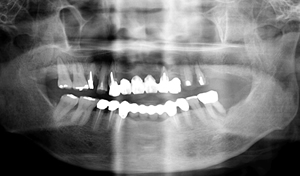

治療前

治療後

上顎オールオン4 、下顎インプラント埋入治療 |

| 治療内容 | 上顎オールオン4 、下顎インプラント埋入 |

| 治療期間 | 6ヶ月 |

| 費用 | 3,630,000円(税込) |